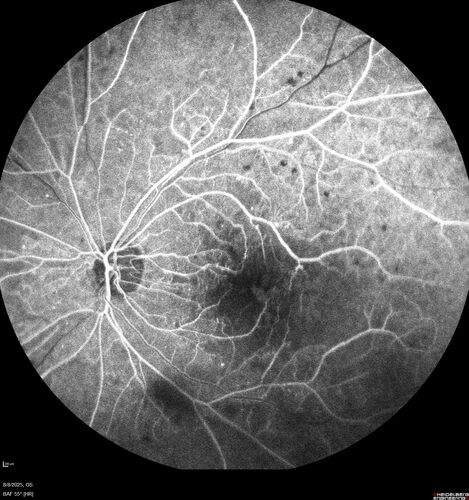

NPDR and Severe macular ischemia sudden vision loss

60 year old female with sudden vision loss OD 1 week ago. VA 20/63, 20/200. OCT-A and FA shows severe macular ischemia OU